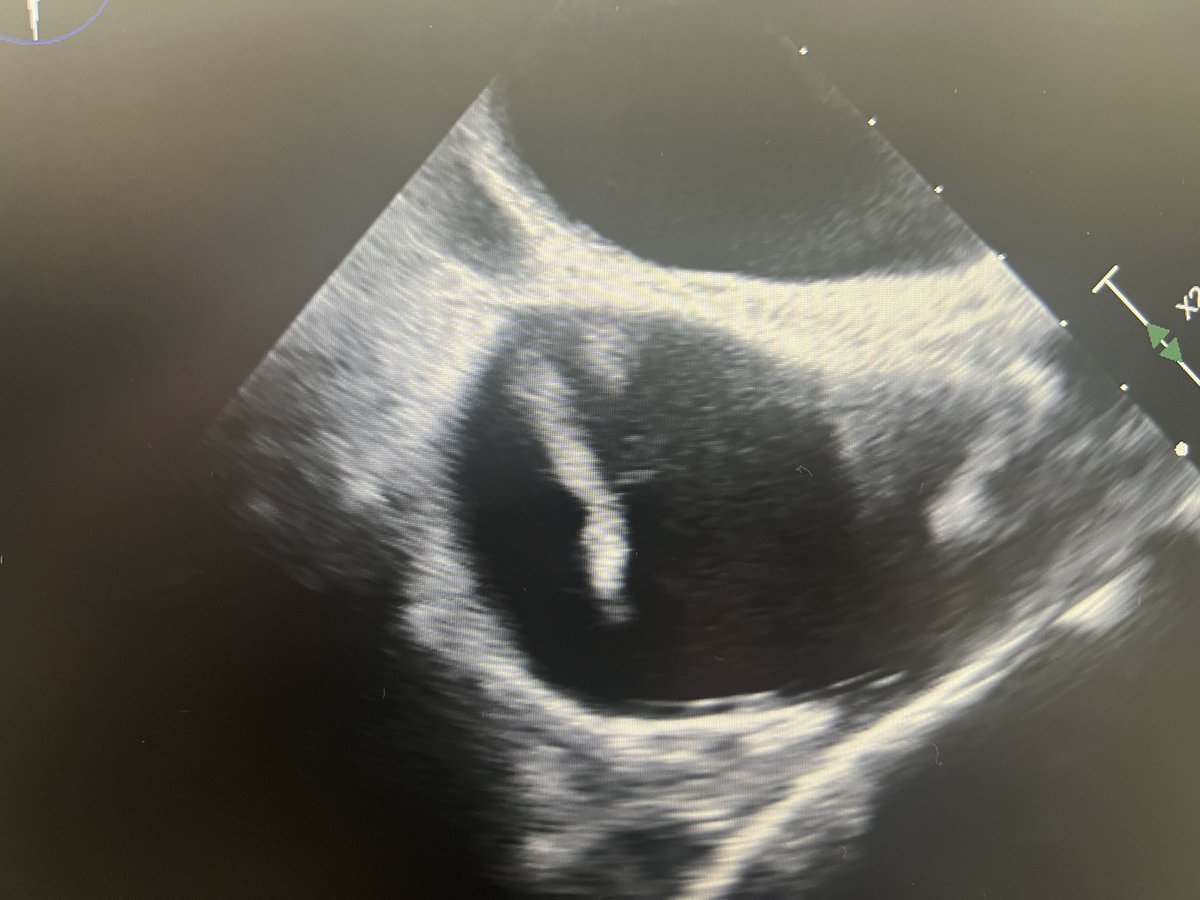

Proud to launch our official ECMO program at @mercy_health St Vincent Medical Center, Toledo. A step toward enhancing ability to care for sickest patients in community with life threatening cardio-pulmonary illnesses. Thanks to entire leadership and steering committee. @tcctoledo